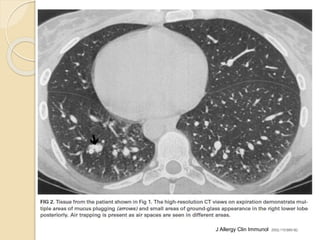

Bronchiectasis : cylindrical when bronchus taper and is 1.5 to >3 times caliber

of diameter of adjacent artery

J Allergy Clin Immunol 2002;110:685-92.